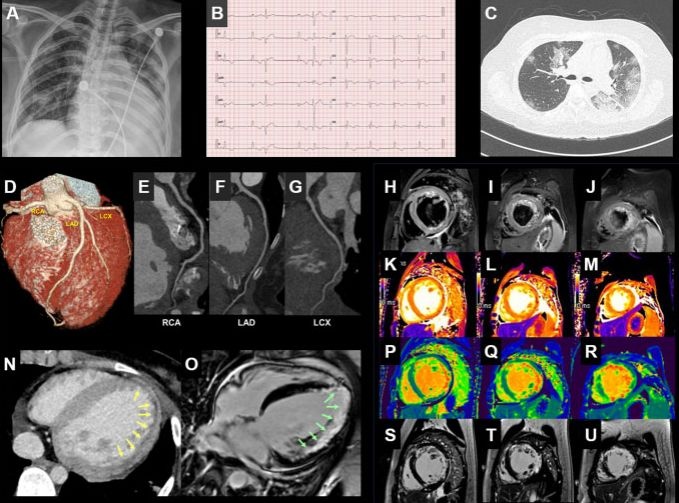

°è¸í´ë ´ë±¸µ¿»êº´¿ø ±èÀÎö·ÇѼº¿í ±³¼öÆÀÀº ÃÖ±Ù À¯·´½ÉÀåÇÐȸÁö(EHJ)¿¡ Äڷγª19 È®Áø ÈÄ ±Þ¼º ½É±Ù¿° Áõ»óÀÌ ³ªÅ¸³­ 21¼¼ ¿©¼ºÀÇ »ç·Ê¸¦ º¸°íÇß´Ù.

ÇØ´ç ȯÀÚ´Â Äڷγª19 È®Áø ÆÇÁ¤À» ¹Þ°í óÀ½ °è¸í´ë ´ë±¸µ¿»êº´¿øÀ» ¹æ¹®ÇßÀ» ´ç½Ã, ¿­, ±âħ, °¡·¡, ¼³»ç, È£Èí°ï¶õ Áõ»ó µîÀ» º¸¿´À¸¸ç ±âÀúÁúȯÀº ¾ø¾ú´Ù.

ÇÏÁö¸¸ ÀÔ¿ø ÈÄ °Ë»ç¿¡¼­ ½É±Ù ¼Õ»ó ¿©ºÎ¸¦ È®ÀÎÇÒ ¼ö Àִ ǥÁöÀÎ Troponin I ¼öÄ¡°¡ 1.26ng/mL·Î Á¤»ó ¼öÄ¡ÀÎ 0.3ng/mLÀÌÇÏ º¸´Ù ÈξÀ ³ô¾Ò°í ½ÉºÎÀü Áø´Ü ÁöÇ¥ÀÎ NTproBNP ¼öÄ¡µµ 1929pg/mL(<125pg/mL)¿¡ ´ÞÇß´Ù.

¿¢½º¼± ¿µ»ó°ú ½ÉÀüµµ °Ë»ç¿¡¼­´Â ½ÉÀåºñ´ë¿Í ½É½ÇÁ¶±â¼öÃà µîÀÇ Áõ»óÀÌ È®ÀεƴÙ.

ȯÀÚ´Â ÇÑ ´Þ °¡·® ÀÔ¿ø Ä¡·á ÈÄ Äڷγª19 ¿ÏÄ¡ ÆÇÁ¤À» ¹Þ°í Åð¿øÇÑ »óȲÀÌ´Ù. ÇÏÁö¸¸ ½ÉÀå ±â´ÉÀÌ ¿ÏÀüÈ÷ ȸº¹µÇÁö ¾Ê¾Æ ¿©ÀüÈ÷ ÁÖ±âÀûÀ¸·Î ¿Ü·¡ Ä¡·á¸¦ ¹Þ°í ÀÖ´Ù.